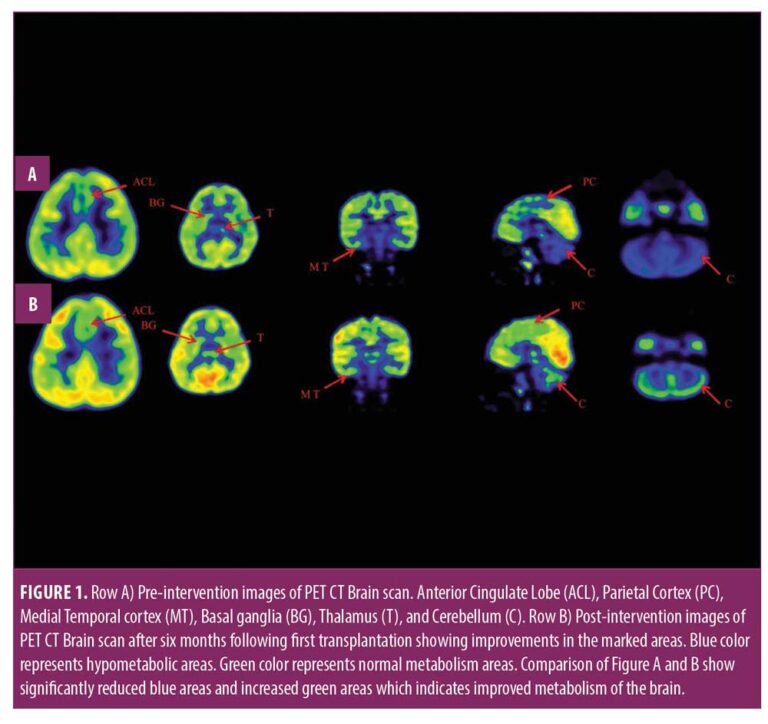

在認(rèn)知上,由于他定期上學(xué),他的注意力持續(xù)時(shí)間和坐姿耐受力也得到了改善。GMFM分?jǐn)?shù)從60.67提高到67。GMFCS等級(jí)由3級(jí)提升至2級(jí);FIM評(píng)分從97分提高到99分。比較第一次細(xì)胞治療之前和之后7個(gè)月期間進(jìn)行的腦部PET CT掃描結(jié)果,發(fā)現(xiàn)前扣帶回葉、頂葉皮層、內(nèi)側(cè)顳葉皮層、丘腦、基底神經(jīng)節(jié)和小腦(表1)。

在此,我們通過(guò)客觀量表(如FIM、GMFM和GMFCS)和正電子發(fā)射計(jì)算機(jī)斷層掃描腦神經(jīng)影像對(duì)比研究來(lái)監(jiān)測(cè)細(xì)胞療法后的療效。在16個(gè)月的治療過(guò)程中,GMFM評(píng)分從60.67分提高到81.88分,其中坐的領(lǐng)域從59分提高到60分,爬行和跪的領(lǐng)域從32分提高到40分,站的領(lǐng)域從6分提高到27分,走、跑和跳的領(lǐng)域從8分提高到32分。GMFCS 分級(jí)從第3級(jí)提高到第2級(jí),因?yàn)楹⒆幽軌蝌v出雙手坐在椅子上,能夠在沒(méi)有幫助的情況下在平整的地面上行走和奔跑,還能夠扶著欄桿爬樓梯。FIM分?jǐn)?shù)從91分提高到99分,這表明他的功能狀況有所改善。

這項(xiàng)研究表明,多種干細(xì)胞療法結(jié)合神經(jīng)康復(fù)可有效改善腦癱患者的粗大運(yùn)動(dòng)功能和功能獨(dú)立性。自體BMMNC多次移植后進(jìn)行強(qiáng)烈的神經(jīng)康復(fù)可加快神經(jīng)再生過(guò)程,這反過(guò)來(lái)又反映了患者殘疾程度和生活質(zhì)量的積極結(jié)果。PET CT掃描可以有效地用于監(jiān)測(cè)干預(yù)后細(xì)胞水平發(fā)生的變化。因此,多細(xì)胞療法是安全、可行的,并且可以有效地與腦癱的神經(jīng)康復(fù)相結(jié)合作為增強(qiáng)治療。